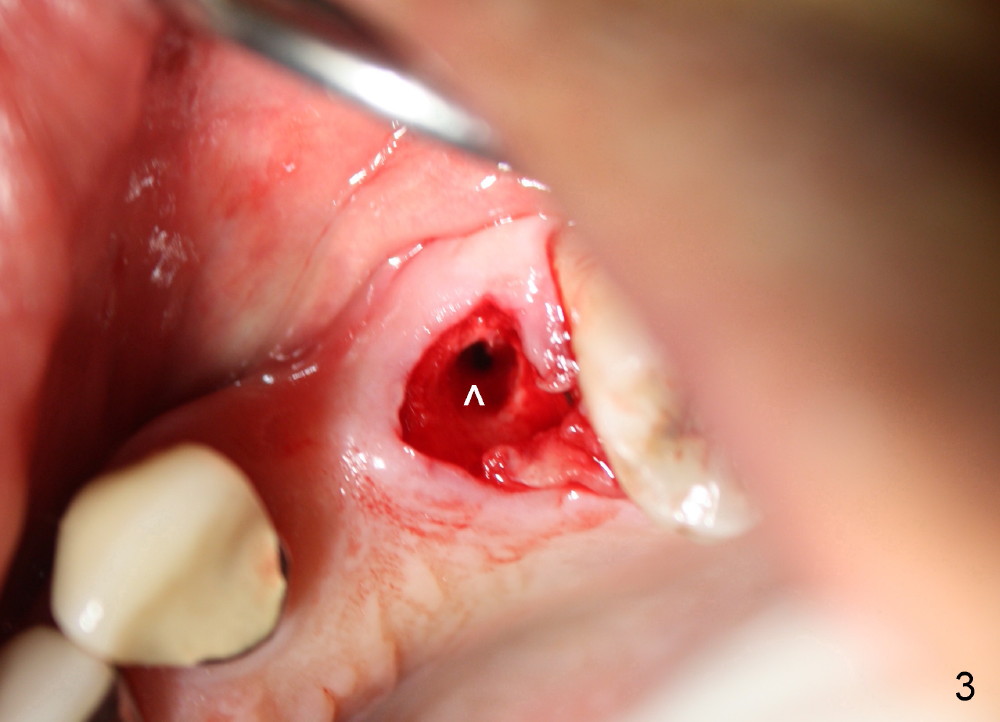

The anterior retainer is kept as a crown at #11 (Fig.2: C), whereas the residual root at the site of #13 is extracted with apical perforation (Fig.3 ^). It is confirmed by Fig.4 (<). To close the perforation, an osteotomy is initiated on the palatal wall of the socket with a 2 mm osteotome (Fig.5 insert: circle). As the osteotomy is being enlarged by a 3 mm osteotome, the bone between the original socket and the osteotomy is being pushed buccally. The former is being closed (Fig.5). The osteotomy is finished with combination of osteotomes and reamers. Fig.6 shows that a 5x14 mm tap is inserted at the site of #13 and that the sinus floor is lifted. In fact the sinus membrane is partially torn at the osteotomy, which is repaired by insertion of Colla-form Dressing (Impladent), followed by autogenous bone (harvested from reamers) mixed with Osteogen (Impladent). A 5x14 mm implant is placed at the site of #13 with insertion torque more than 60 Ncm (Fig.7: I). An incision is made at the site of #12 to start osteotomy with insertion of a parallel pin (Fig.7 P). A 3 mm reamer is kept in place for position confirmation (Fig.8 R). Due to ridge atrophy (Fig.2 arrowheads), a much smaller, but longer implant is placed at the site of #12 (Fig.9: 4x17 mm). The autogenous bone harvested from #12 osteotomy is placed in the buccal gap of #13, followed by insertion of Colla-form Dressing (Fig.10 M). To protect the membrane, a short abutment (4x3 mm) is temporarily placed (Fig.9,10 A) and perio dressing (Fig.9 D) is applied around the abutment and the interproximal areas of the neighboring teeth. Usually perio dressing dislodges around 1 week postop, particularly for a large edentulous space. In this case, the dressing is quite stable 11 days postop: the abutment (Fig.11 A) appears to contribute to retention of the dressing (D).